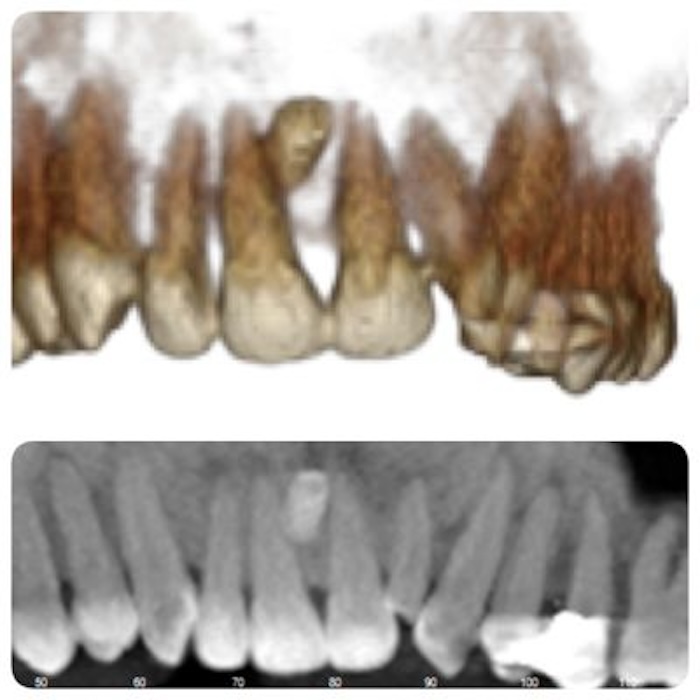

Dientes Supernumerarios

Los dientes supernumerarios o dientes de más corresponden a la existencia de un número excesivo de dientes en relación con el número de dientes normal.

La mayoría de los dientes supernumerarios se ubican en el maxilar con una fuerte predilección por la región anterior. Llamados mesiodens se localizan detrás de los incisivos permanentes.

Cuando la erupción del diente permanente se halla alterada, se recomienda una valoración radiográfica antes de los 9 años de edad.

El tratamiento de los dientes supernumerarios es la extracción, y el momento de ejecutarlo depende de la clase y posición del diente y del efecto que tenga sobre los dientes vecinos, se prefiere posponer la intervención quirúrgica hasta los 8 a 10 años de edad, cuando el desarrollo radicular del incisivo central y lateral esté casi completo.

"El diagnóstico y el tratamiento tempranos son necesarios para una buena oclusión"